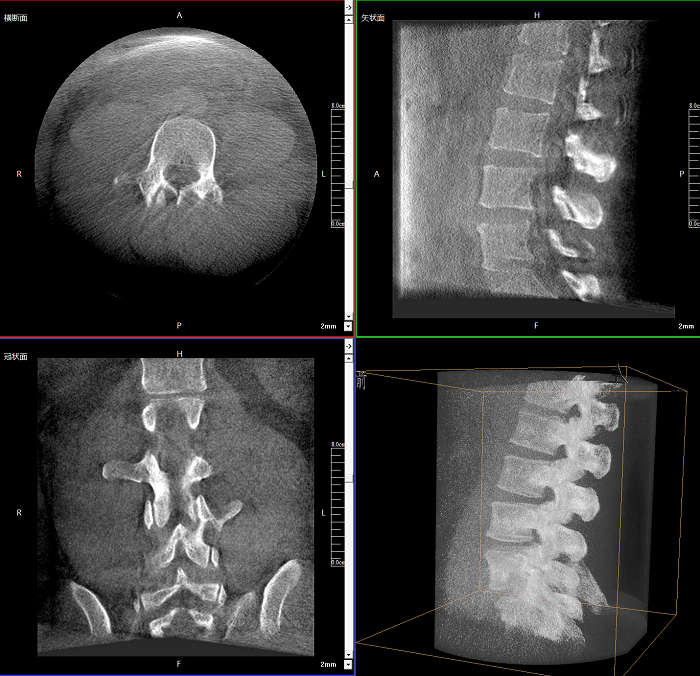

術(shù)中實(shí)時(shí)生成橫斷面、矢狀面、冠狀面及三維影像,可在任意切面、任意角度評估植入物和解剖結(jié)構(gòu)的相對位置。

術(shù)中CT檢查 減少翻修概率

通過術(shù)中三維影像的檢查,可以立即發(fā)現(xiàn)植入物的錯(cuò)位,減少不必要的第二次手術(shù),減少并發(fā)癥概率以及感染風(fēng)險(xiǎn)。

較9英寸常規(guī)平板視野提升100%,幫助醫(yī)生迅速判斷椎體節(jié)段,定位手術(shù)部位。

Clinical picture

臨床圖片